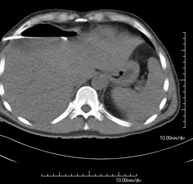

- Abdomen CT

Diagnostic test that involves obtaining high-definition anatomical images of the abdomen (liver, gallbladder, bile duct, pancreas, spleen, stomach, intestines, kidneys, vascular structures, bladder, uterus and ovaries, etc.) using CT (computed tomography) equipment. These images are then studied at a workstation capable of producing two-dimensional reconstructions in different spatial planes, and also 3D (volumetric) reconstructions. Most studies require the use of iodinated contrast to improve image definition.